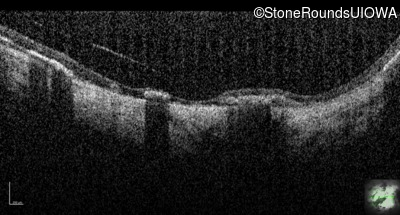

Optical Coherence Tomography - Right - Light Perception

Exemplar / OCT Stack